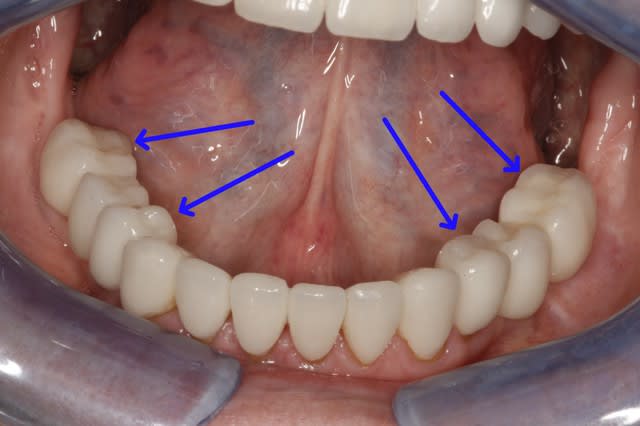

un truc comme ça?

46 loupé mais 44/47?